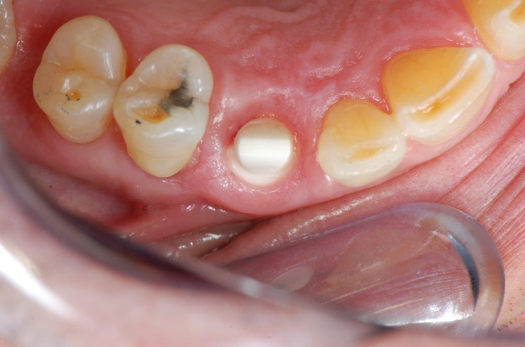

Fig 1. Preoperative surgery.

Figure 1

A patient presented to the dental practice with multiple root fractures, recurrent caries, and a need for significant crown-lengthening procedures, endodontic therapy, post and cores, and long-term restorations. The patient considered the entire volume of therapy and was not interested in undergoing treatment with less than a satisfactory long-term prognosis. The patient was given two dental-implant options and chose to move forward with ceramic dental implants.

Figure 1 and Figure 2 depict the preoperative image and subsequent removal of three posterior teeth, immediate placement of zirconia-oxide ceramic dental implants, and soft-tissue augmentation with platelet-rich fibrin (PRF) to enhance the soft-tissue architecture surrounding the ceramic implants. The teeth were removed atraumatically and without suture placement. Because the implants were one-piece in stature (the abutment was incorporated into the implant), the recommendation was to splint the multiple units to minimize the lateral forces from mastication, swallowing, and tongue movement.